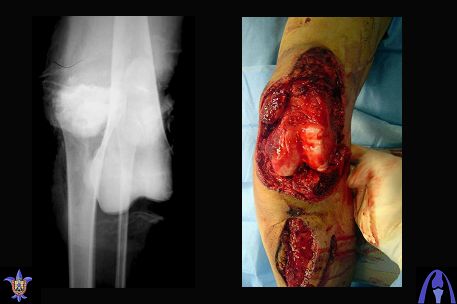

Bolnoi 27 let, DTP, Motorcycle trauma, postupil v kreane tiajelom sostoianii, osnovnia trauma- otkrity totalny vivih levogo kolennogo sustava s povrezdeniem malogo bersovogo nerva, tracionnoi povrezdenia podkolennoi arterii bez narushenia selostnost' sosuda, pomosh' okazanno v nujnum obmeme, kakoe ze mnenie uvazaemih kolleg naschet dalneshego vvedenia bolnogo? Castro

На ренгенограмме хорошая аппозиция костей коленного сустава, но надколенник находится подозрительно высоко, поэтому необходимо убедиться в отсутствии повреждения связки надколенника.

Если состояние мягких тканей не вызывает сомнения, тогда надо проводить профилактику эквинуса брейсом.

Снимки прошлых публикации из моего Power point